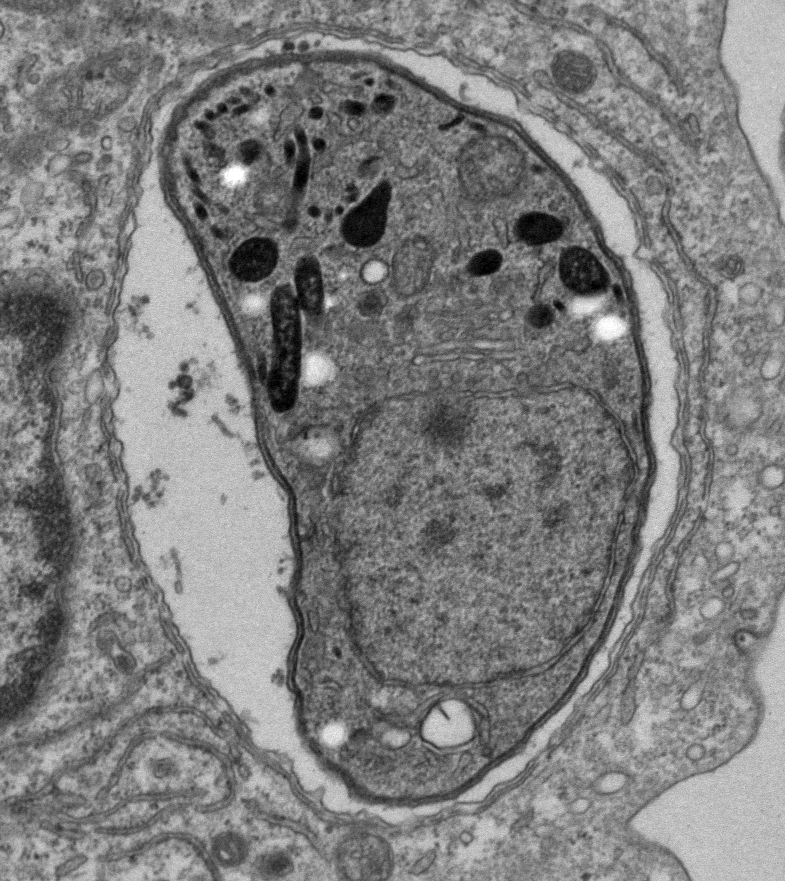

Transmission electronic microscopy image of Toxoplasma gondii

Credit: Masahiro Yamamoto